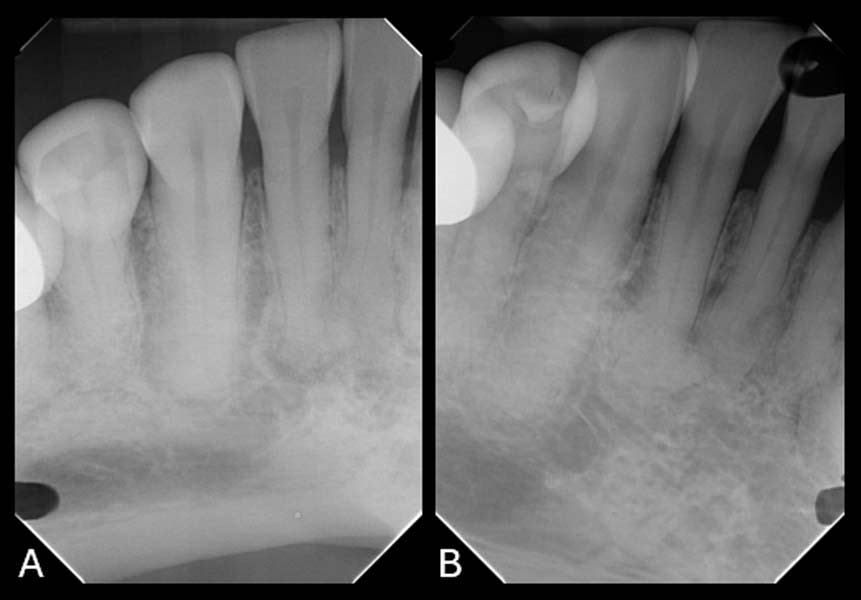

Upon review of the FMX, multiple quadrants of hypercementosis were noted, including all mandibular quadrants and the maxillary left quadrant, and an electric pulp test of the mandibular right posterior quadrant demonstrated vital pulps, with the exception of tooth No. 30 (Figure 1). Teeth Nos. 29 and 30 had no mobility and were percussion negative with periodontal pocket depths buccally of 3 mm and 2 mm and distally of 3 mm and 4 mm, respectively. There was no pain on percussion of tooth No. 31. From the periapical radiographs, the roots of teeth Nos. 29 and 30 were noted to be grossly thickened, bulbous, and blunted due to a fairly symmetrical deposition of a radiopaque material on their surfaces (Figure 2, right). Also noted, both the second premolar and first molar had obvious concrescence of cementum, most pronounced at the first molar (Figure 2, right). In addition, tooth No. 30 incipient PDL space widening and generalized posterior alveolar osseous bone loss were also noted.

The patient’s atypical distribution raises important questions about cementum biology, particularly regarding the deposition of cementum in regions subject to differing functional loads. Typically, posterior teeth are exposed to high occlusal forces, which may influence cementum proliferation. Reviewing intraoral photographs captured in 2025, heavier than expected anterior occlusion was noted. However, the presence of concrescence in the mandibular anterior region, where occlusal forces should be minimal, suggested that occlusal forces may have been involved and may have played a role in the pathogenesis of cementum hyperplasia.